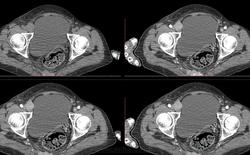

Матка смещена влево и резко увеличена, неправильной формы, размером 105*75*155 мм, неоднородной структуры, с четкими бугристыми контурами, с неоднородным и кольцевидным накоплением контраста.

Придатки справа увеличены размерами до 49 мм в диаметре с неоднородным и кольцевидным накоплением контраста и с кистозным компонентом размером 50*45*67 мм, не накапливающий контраст. Дополнительно определяется мягкотканое образование в правом паховом канале размерами 36*25*27 мм, с четкими бугристыми контурами, неправильной формы, с равномерным накоплением контрастом, вызывающая локальную деформацию мочевого пузыря, связи с сосудисто-нервным пучком не наблюдается.

В преддверье влагалища определяется объемное образование неправильной формы с равномерным и кольцевидным накоплением контраста размерами 32*40*46 мм. В толще жировой клетчатки в проекции правой паховой области определяется объемное образование размером до 31 мм в диаметре, равномерно накапливающее контрастное вещество.

Мочевой пузырь деформирован, оттеснен вправо, резко наполнен, стенки его ровные, неутолщены.

Отмечается мягкотканая инфильтрация правой части крестца и с остеолитическим компонентом, неправильной формы, размерами 47*71*43 мм, со слабочетикими контурами, с неравномерным накоплением контарста, распространяющееся до основания копчика и в прилежащие мягкие ткани малого таза и ягодичной области. Связи между вышеописанным образованием не определяется. Структура оставшейся крестцовой кости и костей копчика остеопорозна.

Кровеносные сосуды расположены обычно. Парааортально отмечается мягкотканый конгломерат с четкими бугристыми контурами на протяжении до 84 мм и шириной до 65 мм, неравномерным накоплением контраста.